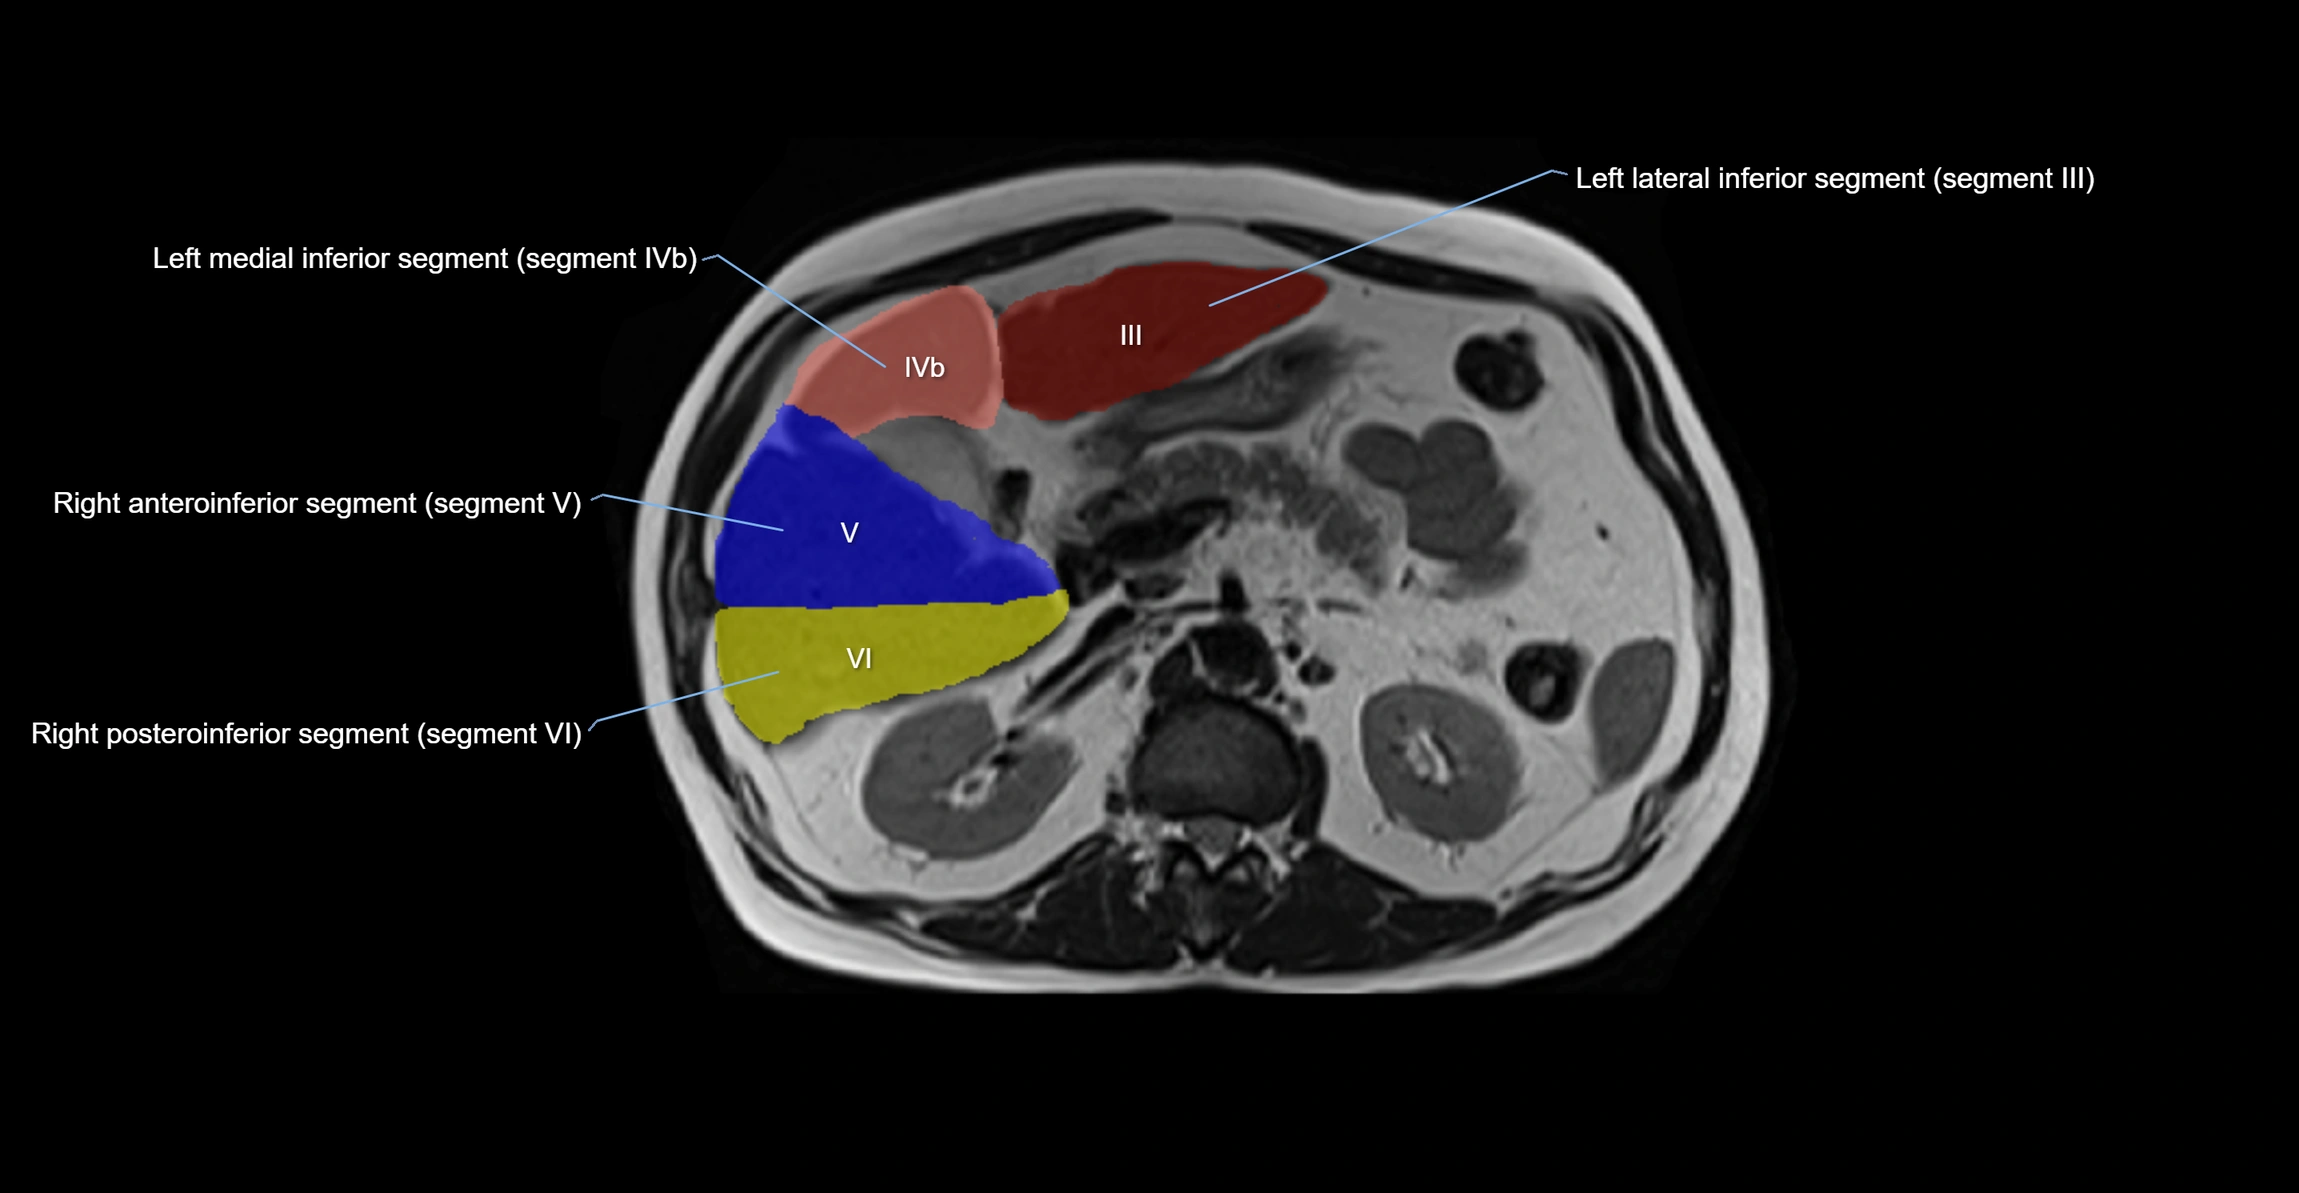

The caudate lobe of the liver is a distinct anatomical subdivision of the liver, designated as segment I in Couinaud’s classification. It lies on the posterior surface of the liver, between the fissure for the ligamentum venosum (left boundary) and the groove for the inferior vena cava (IVC) (right boundary). Superiorly, it is related to the posterior liver surface, and inferiorly it is separated from the left lobe by the porta hepatis.